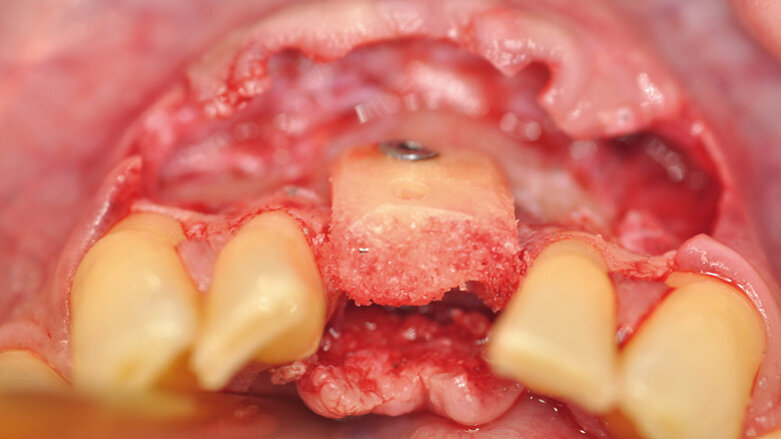

Horizontální augmentace alveolu pro zavedení implantátu.

Materiály a metody

Celkem patnáct pacientů bylo ošetřeno stejným lékařem v Godt Smil Odense od listopadu 2013 do března 2015. Devět pacientů bylo mužského a šest ženského pohlaví. Nejmladšímu pacientovi bylo dvacet šest let a nejstaršímu sedmdesát osm. U tě-

chto patnácti pacientů bylo zavedeno devatenáct alogenních kostních bloků za účelem horizontální augmentace atrofického alveolárního výběžku jak v dolní, tak v horní čelisti před zavedením implantátu. Všichni pacienti byli celkově zdrávi, jeden z nich byl kuřák. Pokud bylo třeba, podstoupili před chirurgickým zákrokem všichni pacienti parodontologickou léčbu.